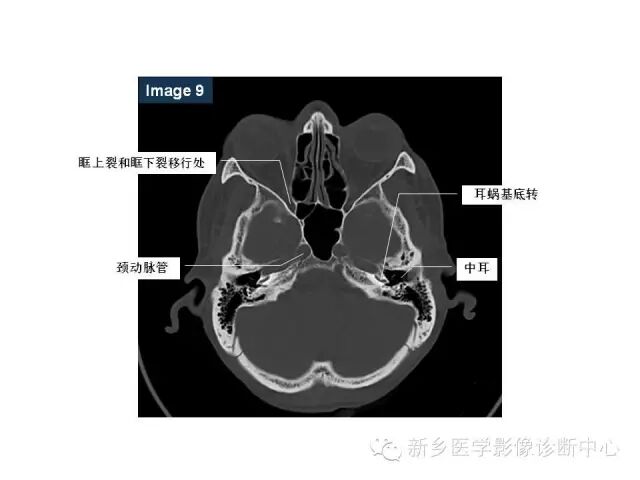

鼻咽部的详细解剖(含各个孔道)

来源:新乡医学影像诊断中心